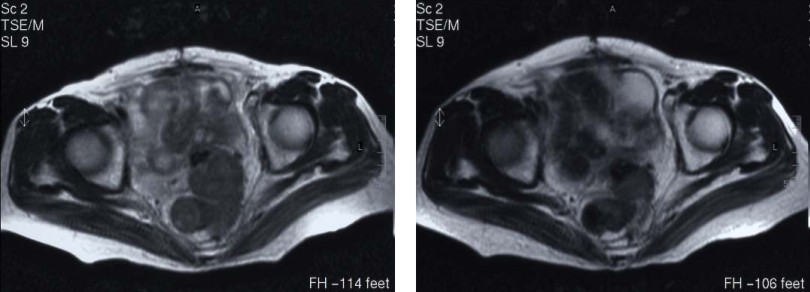

病例5 结肠癌

A 治疗前DSA B 灌注CMI化疗药物立即造影瘤染色明显减少

C 治疗前MRI见乙状结肠病灶 D 治疗后病灶缩小